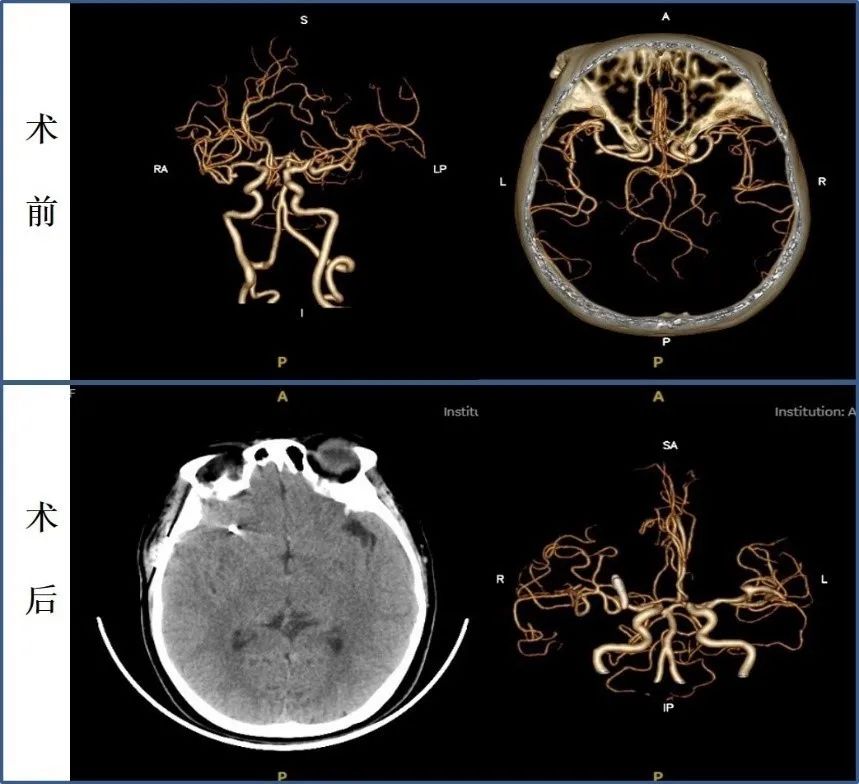

不久前,53岁的徐女士因头痛到青大附院就诊,经详细检查确诊为颅内动脉瘤。丰育功主任、郭品副主任迅速制定手术方案,成功实施“开颅动脉瘤夹闭术”。在整个治疗过程中,丈夫刘先生始终陪伴在侧、悉心照料。术后,徐女士恢复良好,一周后便顺利出院。